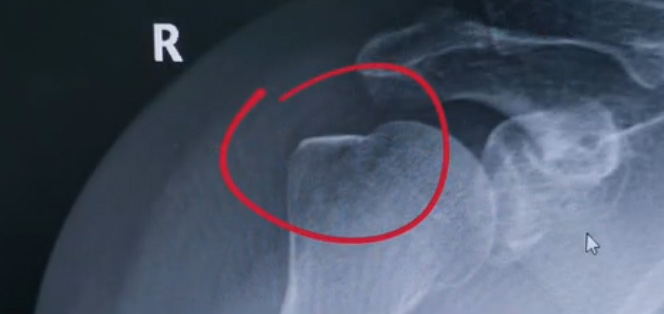

肩關(guān)節(jié)的X射線片子,看到?jīng)]有明顯的骨折,但是實際上已經(jīng)骨折了。那么是如何發(fā)現(xiàn)的呢?醫(yī)生對于做出疾病診斷的時候,會選擇什么樣的檢查方式。也更好的配合醫(yī)生,來解決問題。1米高的地方摔了下來,右側(cè)肩關(guān)節(jié)與地面相撞受傷了。當(dāng)時的胳膊還能活動,疼痛感很明顯,但是在家觀察了一天,這個腫脹沒有明顯的加重。然而問題是什么呢?疼痛始終不能緩解,所以就需要到醫(yī)院檢查。醫(yī)生查看關(guān)節(jié)的受限也很明顯,尤其做外展這個動作的時候,幾乎沒辦法自行完成。肩關(guān)節(jié)內(nèi)的這個韌帶和肌腱可能還沒有發(fā)生嚴(yán)重的損傷。

首先做一個普通的X光檢查,看一看有沒有大的骨折或大的問題。結(jié)果是沒有發(fā)現(xiàn)太嚴(yán)重骨折損傷問題。結(jié)合病史,還是有點疑惑。因為疼的太厲害。x光檢查和他的疼痛之間不匹配,患者沒有骨頭的損傷,疼痛不至于達到這么嚴(yán)重的一個程度。是否有一種情況掩蓋住了病情。這也是X線檢查的通病。x光檢查它是一個二維的檢查,有可能患者肩關(guān)節(jié)啊發(fā)生了骨折。但是它的位置被前方或者側(cè)方的這個骨頭遮擋住了。不是立體的就沒辦法看到后方的情況。想要更加進一步的明確問題,判斷是否有骨頭的損害怎么辦?

進一步就是查CT,可以更全面的角度去判斷問題的所在。就會發(fā)現(xiàn)是否骨折可以看到確實存在著骨折,還好骨折不算嚴(yán)重。可以說是一個骨裂。這個肩關(guān)節(jié)與地面撞擊的時候,暴力沒有達到那么強。讓骨頭整個發(fā)生一個巨大的斷裂,而是造成了一個小的劈裂。適當(dāng)?shù)倪M行一些抗炎止痛藥的使用。適當(dāng)?shù)倪M行一些消腫治療,患者癥狀也就消失了。